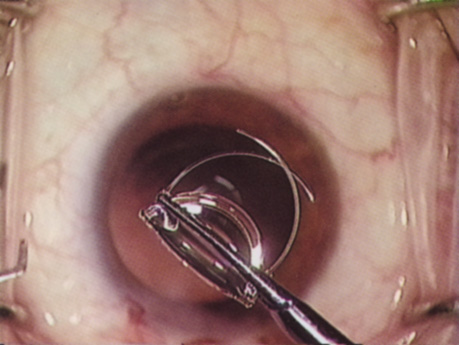

COMPROMISED ZONULES

The introduction of innovative adjunctive devices was able to improve the management of challenging cases. The capsular tension ring introduced independently by Tsutomu Hara37 and Toshiyuki Nagamoto38 in Japan was identified as a major weapon in managing zonular weakness by Ulrich Legler and Bernd Witschel of Germany.39 The CTR came to the United States in 1993,40 after which modifications by Robert Cionni,41 Iqbalk Ahmed and Alan Crandall,42 and Burkhard Dick were developed. Iris reconstruction had been primarily limited to suture techniques developed by Malcolm McCannel43 and later Steven Siepser.44 The prosthetic irides were introduced by German surgeons, Ranier Sundmacher45 and Volker Rasch,46 and brought to the United States by Kenneth Rosenthal and then Robert Osher in 1996.47 Although many devices had been developed to mechanically open the small pupil, it was the stretch technique developed by Luther Fry that greatly simplified these difficult cases.48 Improving visibility by staining the anterior capsule of the white cataract was introduced by Masayuki Horiguchi from Japan (ICG)49 and Gerritt RJ Melles from The Netherlands (Trypan Blue).50